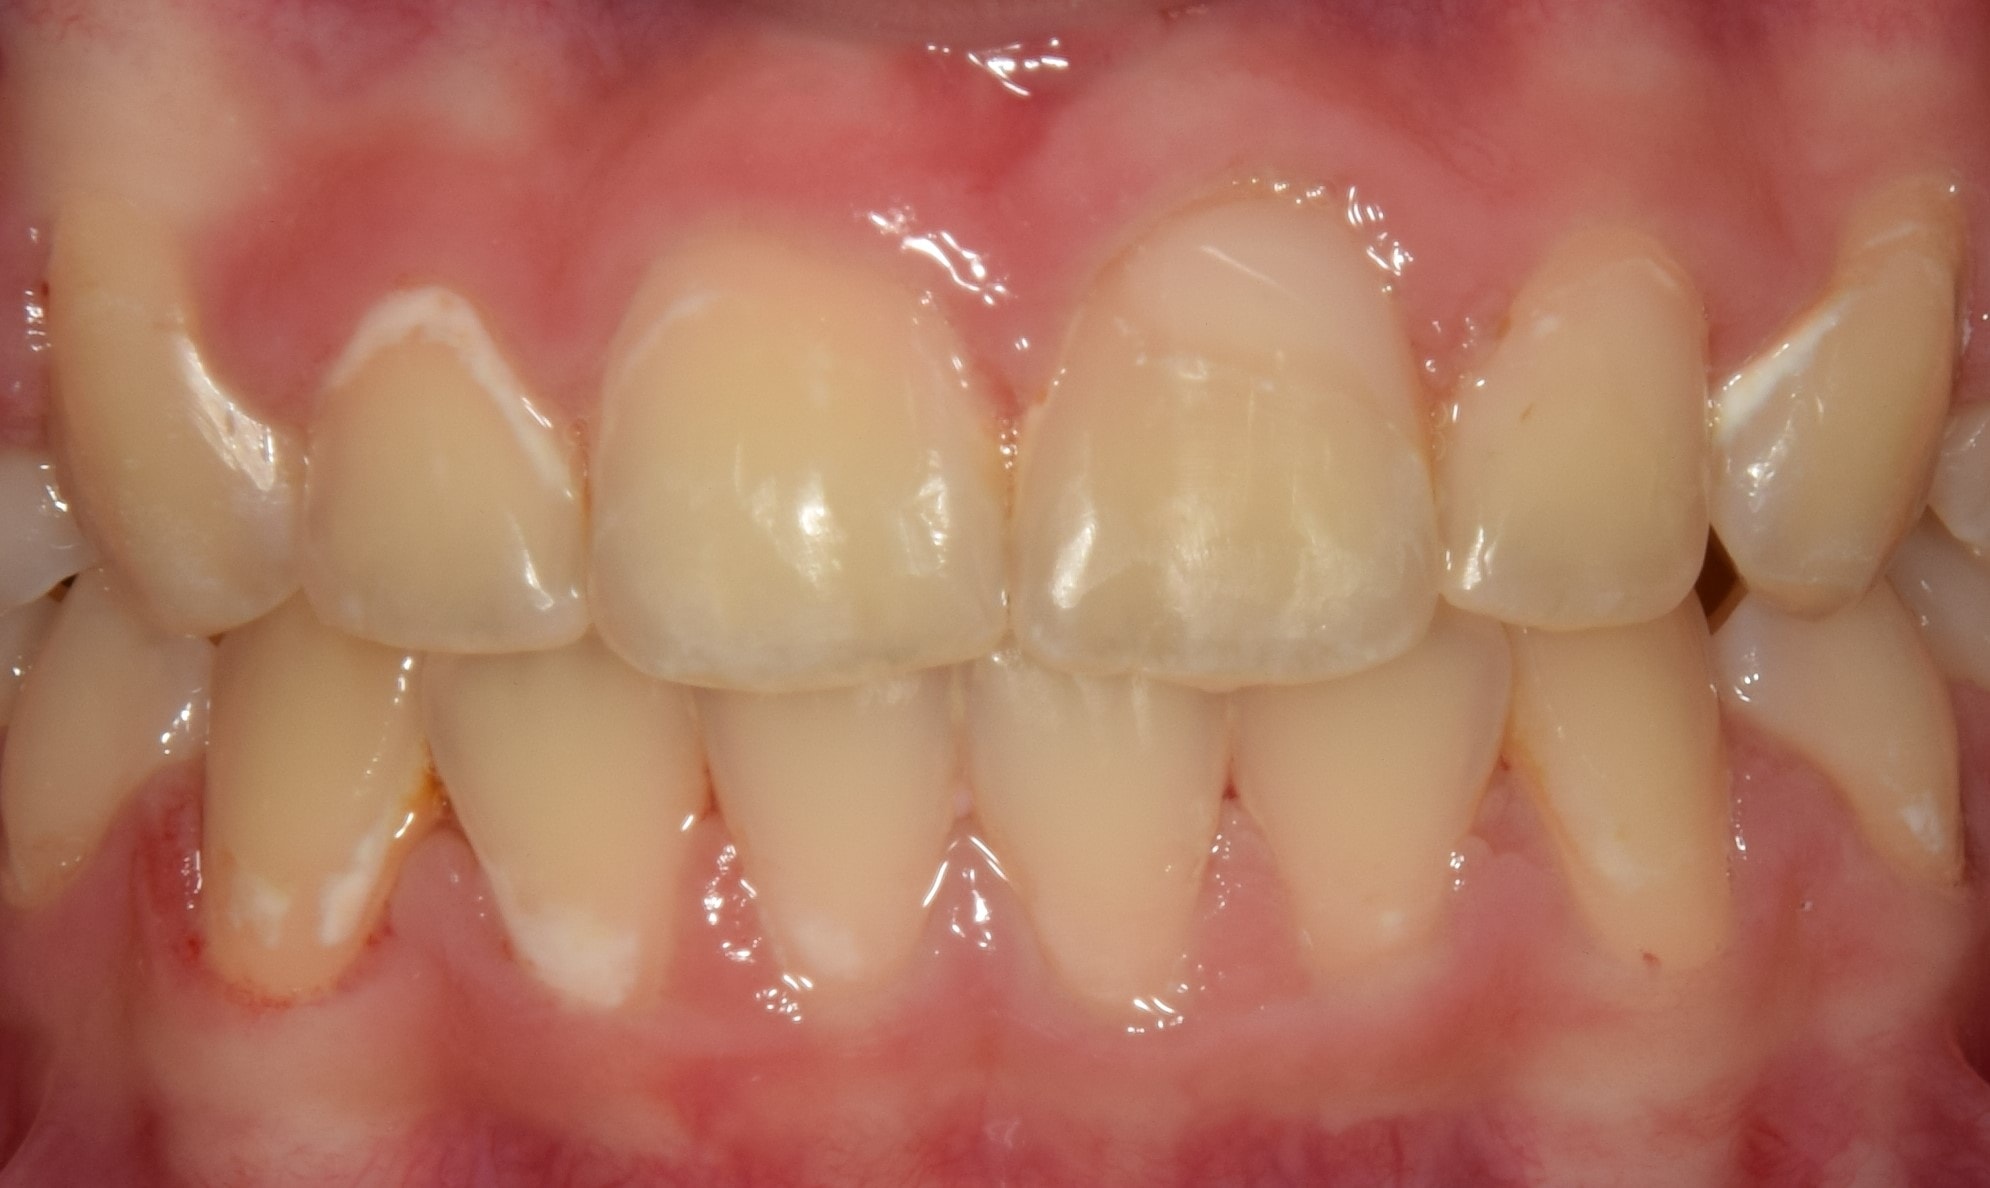

Fotódokumentáció

A fogszabályzó kezelés előtt-alatt-után rendszeresen készítünk fényképeket. Ez egy külön erre a célra összeállított tükörreflexes fényképezőgéppel történik. Nem a legkellemesebb élmény a fogszabályozás során, de utána nagyon jó lesz visszanézni a képeket. Sok fontos információt nyerhetek ki a készített fotókból, olyanokat is, amelyeket esetlegesen szájban nem veszek észre (nagyon kis méretűek), de egy nagy monitoron már könnyedén. A fotódokumentáció tehát még pontosabbá, precízebbé teszi a kezeléseim, és segít a maximum elérésében.